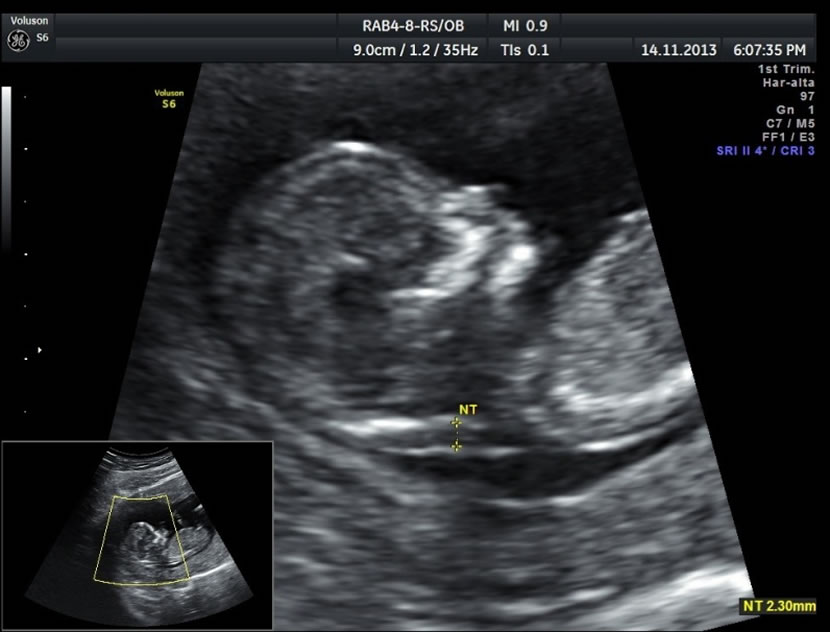

> Para medir el grosor de líquido detrás de la nuca del feto (translucencia nucal)